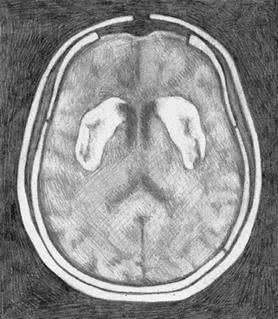

Если, прочитав это, вы почувствовали отчаяние и ужас от мысли, что придется жить без муки и сахара, я хочу заметить, что вот это – голос ваших подавленных дофаминовых рецепторов. Поразительно, насколько сильным может быть это чувство. Кажется, что раз мы отказываемся от этой еды, то в жизни больше не осталось ничего стоящего. Я знаю, как это невыносимо. И вы справитесь, уверяю вас. Дофаминовые рецепторы способны восстанавливаться. И вы снова будете в порядке. Больше чем в порядке – более уверены в себе, свободны от вреда, который эти вещества причиняли вашему мозгу. На рисунке – результаты компьютерной томографии мозга трех разных людей на участке, где в прилежащем ядре располагаются дофаминовые рецепторы. Слева – нормальный мозг, со здоровыми рецепторами, что видно по интенсивности темного участка: чем глубже тень, тем больше неврологическая активность. В центре – снимок мозга человека с кокаиновой зависимостью. Заметьте, что дофаминовый ответ весьма ослаблен. Но посмотрите, справа – мозг человека, страдающего от ожирения. Видите, насколько бледная тень? Дофаминовый ответ еще ниже, чем у человека с кокаиновой зависимостью. Один из ведущих научных принципов заключается в следующем: корреляция не означает причинность. Другими словами, возможно, что не переедание становится причиной истощения дофаминовых рецепторов, а наоборот. Возможно, что мозг человека с ожирением приказывает телу есть так много, потому что его дофаминовые рецепторы изначально были несовершенны. ![]() Нормальный мозг со здоровыми дофаминовыми рецепторами ![]() Мозг человека с кокаиновой зависимостью ![]() Мозг человека, страдающего от ожирения Ученые брали в расчет эту теорию вплоть до мая 2010 года, когда Исследовательский институт Scripps опубликовал статью в журнале «Природа неврологии» (Nature Neuroscience) {46}. Доктор Пол Джонсон и доктор Пол Кенни взяли крыс с нормальным здоровым мозгом и разделили их на две группы. Контрольную группу кормили обычным крысиным кормом. Вторая группа питалась «диетой в стиле кафетерия», включающей в себя бекон, сосиски, чизкейки, бисквиты, глазурь и шоколад, – но только один час в сутки. Третьей группе эта еда была доступна в течение 18–23 часов в день, то есть все, что они могли есть, – пища из «крысиного буфета». Неудивительно, что третью группу постигло ожирение. Но, что более важно, в начале исследования у всех крыс был абсолютно здоровый мозг, в котором впоследствии произошло угнетение дофаминовых рецепторов. Диета в самом деле стала причиной изменений. Наука доказала то, что знает каждый, прошедший через программу «12 шагов»: пищевая зависимость в действительности существует. Она столь же реальна, как кокаиновая. Как героиновая. И с точки зрения физиологии нет никакой разницы. Поначалу исследователи поставили вопрос так: «Итак, еда – это такая же губительная субстанция, как кокаин или героин?» Но сегодня большинство ученых полагают, что речь идет о куда более пагубной зависимости. Пристрастие к сахару и муке В 2007 году в Университете Бордо команда под руководством доктора Сержа Ахмеда вводила крысам кокаин внутривенно до тех пор, пока у животных не выработалась зависимость. Затем грызунам предложили то, чего прежде никогда не давали: сладкую воду. Крыс принудили выбирать между инъекцией кокаина, на котором они уже «сидели», и подслащенной водой. Не имело значения, что использовалось в виде подсластителя, – сахар или его суррогат, – крысы предпочли сладкую воду {47}. Основываясь на этом исследовании, доктор Марк Хайман заявил, что, по его подсчетам, сахар вызывает привыкание в восемь раз сильнее, чем кокаин {48}. В эксперименте, проведенном Исследовательским институтом Scripps, грызуны добровольно перебегали участки пола под напряжением и даже оставались на них, чтобы продолжать есть пищу с высоким содержанием сахара. Степень зависимости можно измерить по силе электротока, который подопытные были готовы выдержать, только бы получить искомое вещество {49}. И степень зависимости у этих крыс достигала порогов кокаиновой или героиновой зависимости. И еще одно наблюдение: когда исследователи переводили крыс с «супераппетитной пищи» на обычный корм, те начинали голодать. Они отказывались есть что-либо, кроме переработанной высококалорийной пищи. Крысы больше не могли потреблять то, что исследователи окрестили «альтернативой салатному меню» {50}. Так откуда нам известно, какая именно пища вызывает зависимость? Некоторые популярные исследования (и исследователи) полагают, что в этом списке сахар, жир и соль {51}. Я не согласна с такой позицией. Во-первых, насколько мне известно, не существует никаких доказательств тому, что соль вызывает привыкание. По правде говоря, с солью еда становится более аппетитной, и мы потребляем больше калорий. В одном эксперименте участники съели на 11 % больше пищи, если она была должным образом посолена {52}. Но аппетитный – это не то же самое, что вызывающий привыкание. |